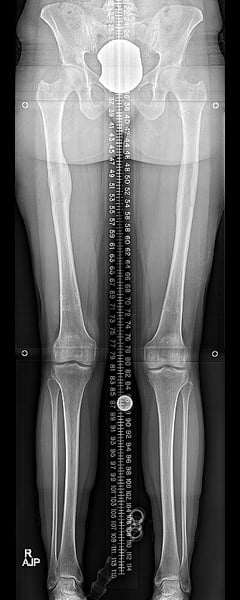

Femurs with nails removed.

The most common increase in height is three inches (or 8 cm) because that is how long the implanted rods extend. If the procedure is repeated in the lower leg bone (the tibia), another 2 to 3 inches can be obtained, for a total of about 5 to 6 inches of added height.

Lengthening three inches is approximately a six-month process. Following surgery and short rest period, the bones are lengthened by less than 1mm (less than 0.04 inches) per day, and the lengthening portion of the treatment takes 3 to 4 months. The bones then take another 6 to 8 weeks to heal and then normal activity can resume. The lengthening rods are removed around 12 months after the initial surgery.

Most patients return to their desired activities at six months from surgery, but each body is different and this can be variable. Nearly all patients will feel even better once the rods are removed at 12 months.